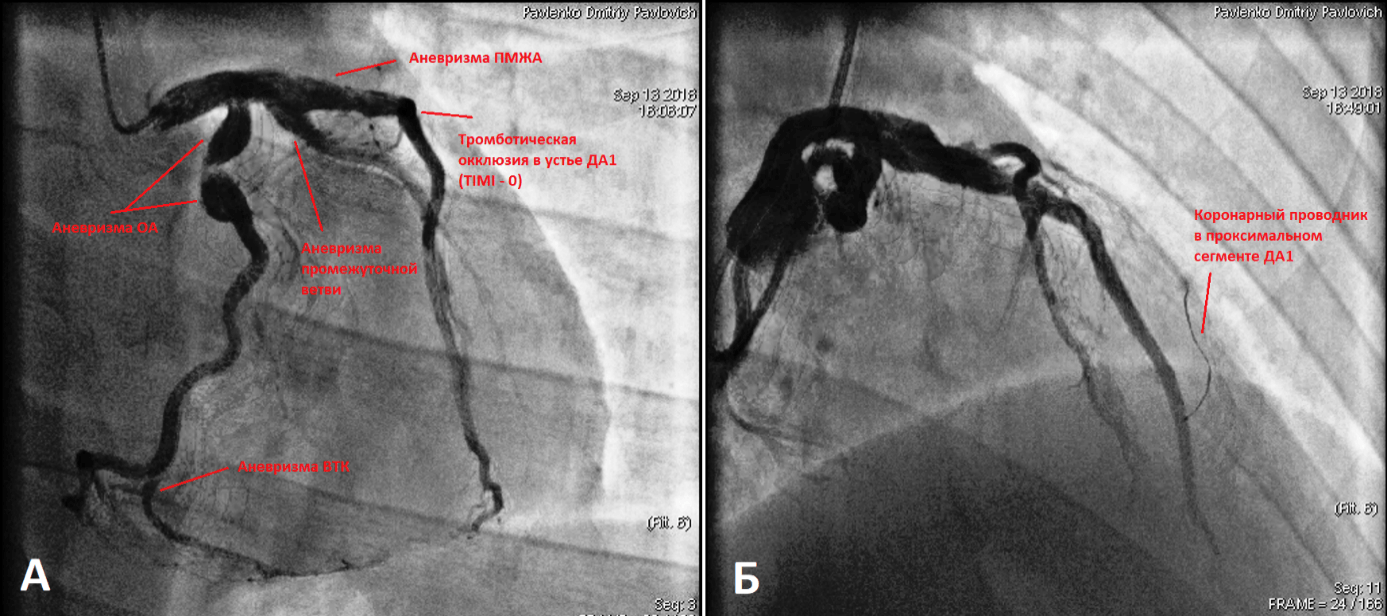

Хроническая окклюзия артерий: причины, симптомы и лечение